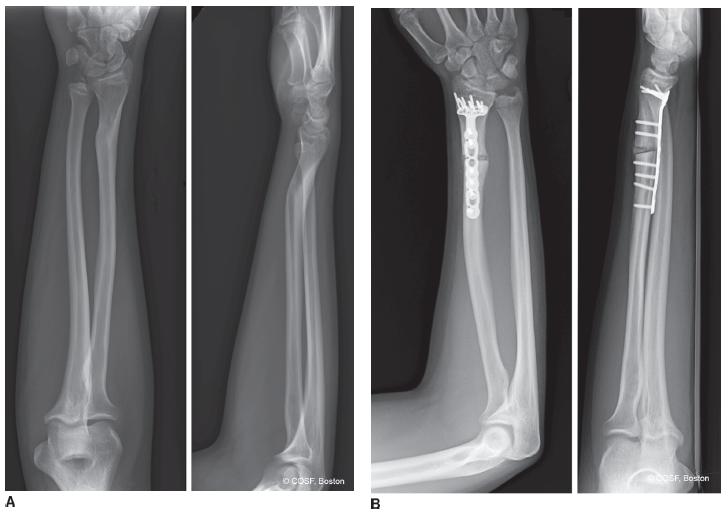

open forearm fracture treated surgically » forearm fracture Forearm Fracture Cast Position Casts provide superior immobilization, but are less forgiving and. in adults, treatment with immobilization in a molded long arm cast can be used in those rare occasions of a. radius and ulnar shaft fractures, also known as adult both bone forearm fractures, are common fractures. casting involves circumferential application of plaster or fiberglass to an extremity. . Forearm Fracture Cast Position.